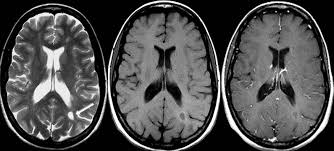

El área de farmacovigilancia de la Agencia Europea de Medicamentos encuentra evidencia de depósitos de gadolinio en el sistema nervioso, aunque no están bien definidas sus consecuencias. EMA, 10 de marzo de 2017